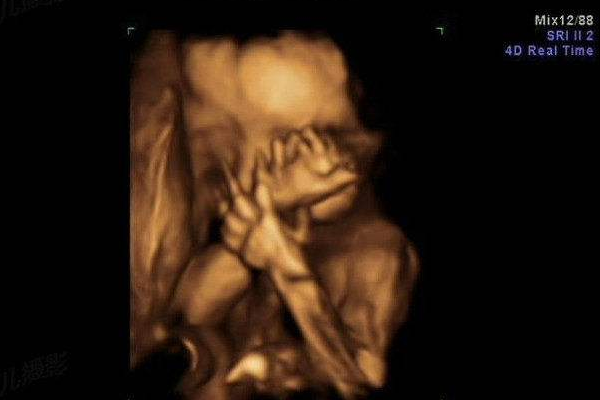

秘密3:胎儿会打嗝

在产前检查时,医生经常看到或听到,孕妇的腹壁出现阵发性、规律性跳动。这种跳动现象一般出现的频率是每分钟15-30次,每次持续时间为3-15分钟,每天出现3-5次不等。

人们以为是胎儿在子宫里缺氧,或是怀疑胎儿有心脏病而感到了胎心跳动,很多产科医生也难以作出解释,甚至有时还会盲目地给孕妇吸氧。

而大量的临床研究发现,这种现象其实是胎儿在打嗝。研究者通过B超观察到,当孕妇的腹壁出现阵发性跳动时,与此同时胎儿的下胸及上腹也出现阵发性抽动,而且膈肌也在上下运动,但胎儿的四肢却并没有随之运动。

其实,很多胎儿都会在子宫里打嗝,不过是有些孕妇难以将它与胎动区别开来,或是反应迟钝而没有感觉到。胎儿打嗝并不是一种异常,只是一种生理现象,不必引起紧张情绪,甚至采取错误的医疗干预。了解胎儿打嗝的现象,对于监测胎儿的健康具有意义。